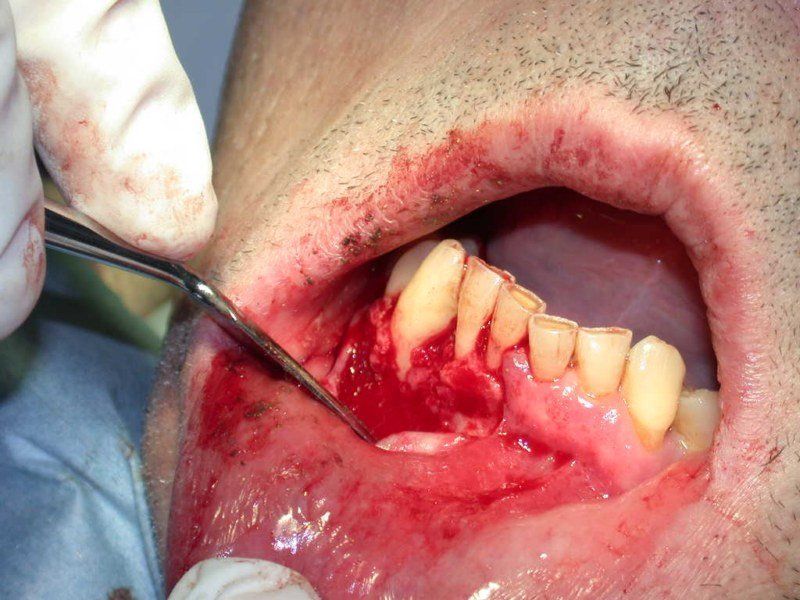

2° Caso: retrazioni gengivali